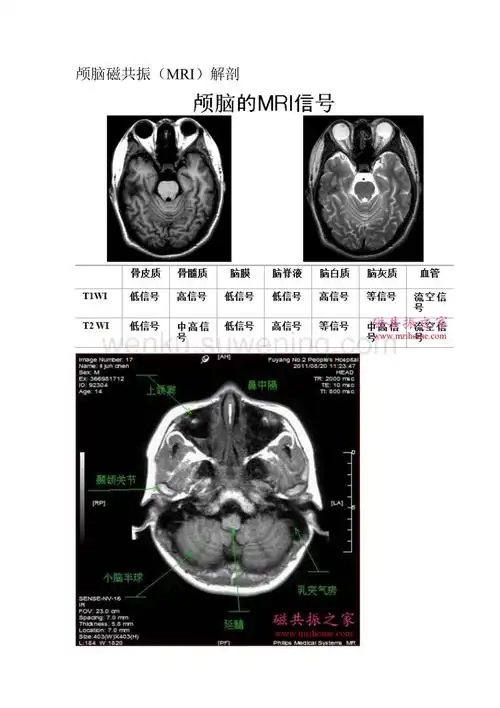

中枢神经系统 医学影像学本科五年制教材(第四版)

颅脑轴位mri解剖